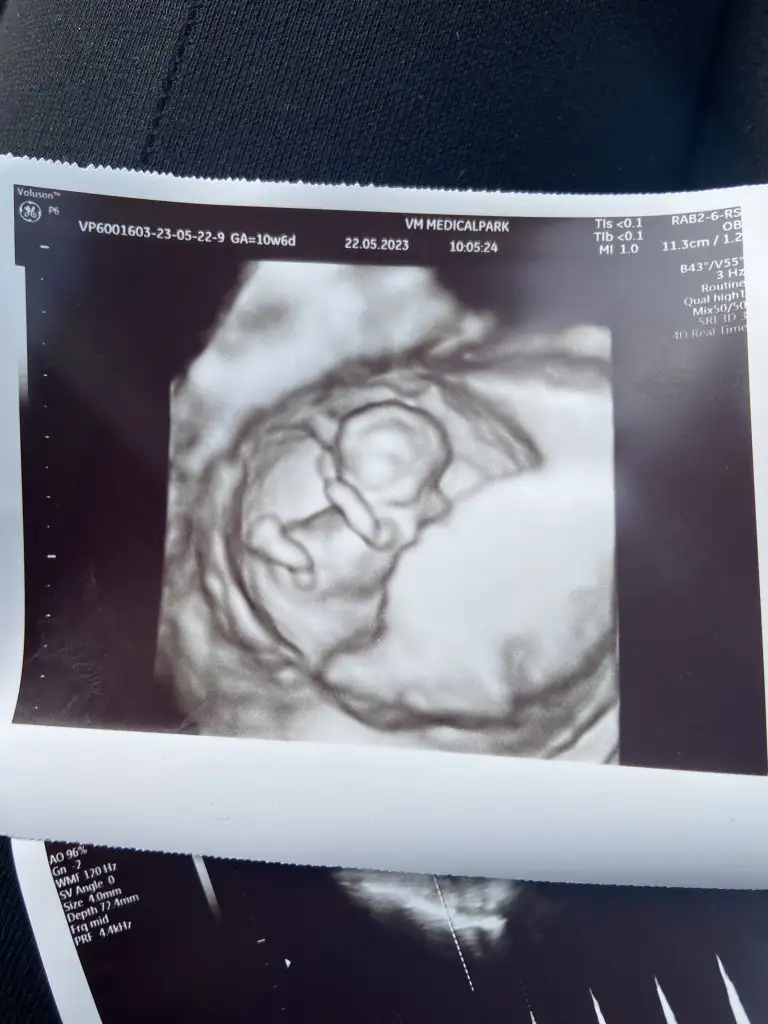

Bebek şükür iyi.

9+4 olmuş.